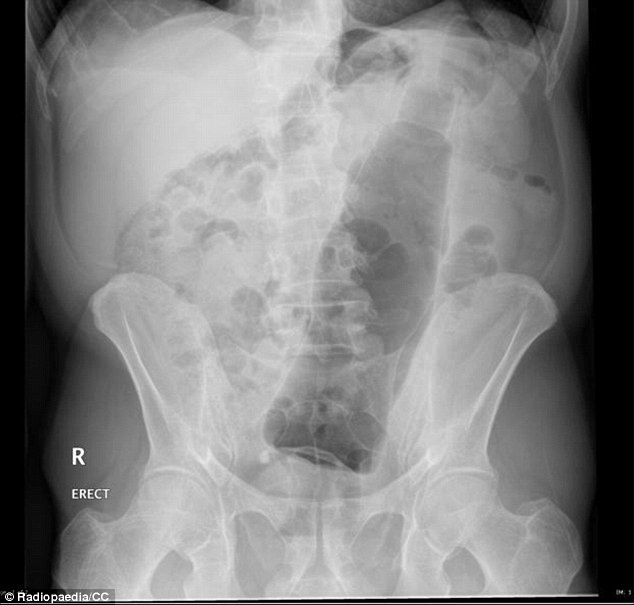

| Dị vật trong ảnh là một chai nước. |